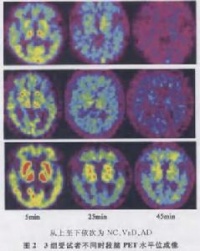

诊断VaD的最基本要素:①痴呆症状;②病史,临床检查和脑影像学检查证实有脑血管疾病(CVD);③两者必须有相关性。

虽然对VaD来说,还没有具诊断意义的特征性的脑CT或MRI检查结果,但如CT或MRI检查无CVD发现,则基本上否定VaD的诊断,并成为AD和VaD鉴别的有力依据。作为考虑诊断VaD的依据,脑影像学检查显示的局部解剖结构的损害及严重度至少达到一定的标准[4,10]。尽管脑损害的体积与痴呆的关系不肯定,但可能存在累加效应。